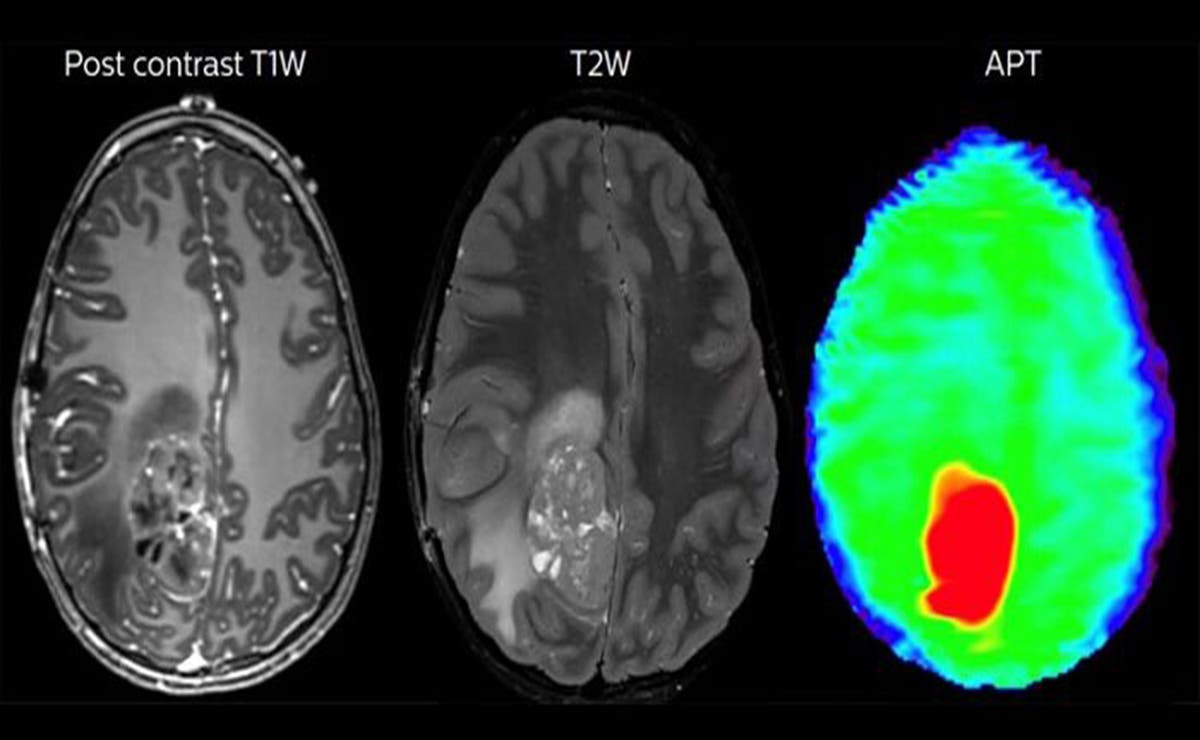

Tecnología Desarrollan microrobots para tratar tumores cerebrales Estados Unidos. – La empresa Bionaut Labas, de Los Ángeles, California, está desarrollado minúsculos dispositivos para atacar tumores cerebrales con una milimétrica precisión. Con... Jazmin Ramossábado, 20 de marzo, 2021